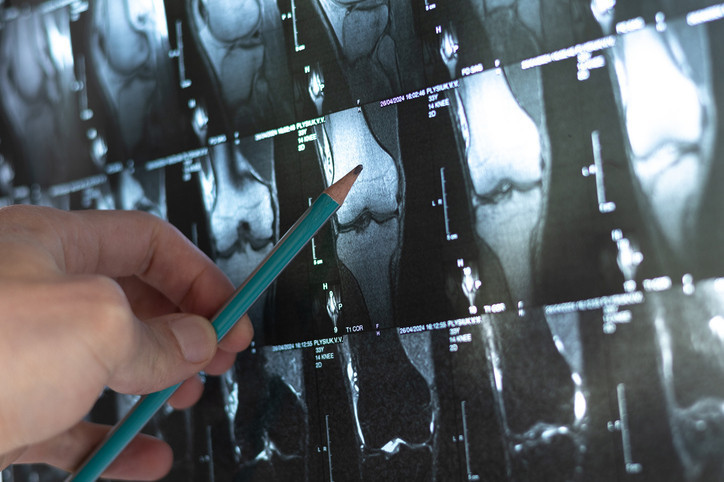

Modern teknoloji ile daha konforlu tedavi

Günümüzde kemik uzatma sürecinde kullanılan yöntemlerden birinin manyetik çiviler olduğunu ifade eden Prof. Dr. Kara, “Manyetik çiviler, kemiğin içinde yer alıyor ve dışarıda hasta herhangi bir aparat taşımıyor.

Hasta elindeki manyetik cihazla günlük 1 mm uzatma yapabiliyor. Biz de süreci yakından takip ediyoruz. Bu yöntem hem daha konforlu hem de iyileşme süresini kısaltıyor” dedi.